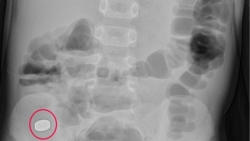

Nguy hiểm khi trẻ nhỏ nuốt nam châm trong đồ chơi

Mới đây, bệnh viện Việt Nam - Thụy Điển Uông Bí (Quảng Ninh) đã tiếp nhận một trường hợp bệnh nhi 5 tuổi, nhập viện do nuốt phải nam châm trong đồ chơi.